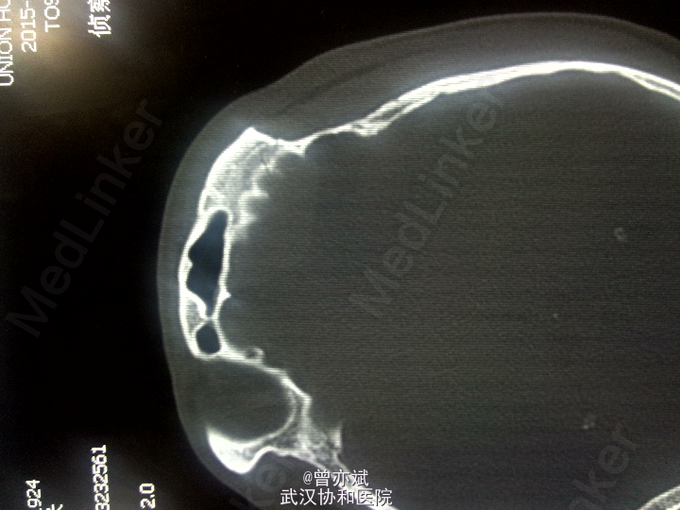

查体:T 36.9℃,P 70次/分,R 20次/分,BP 128/82mmHg,查体不合作,神志浅昏迷,营养发育良好,皮肤及淋巴结未及明显异常,头颅大小正常,无畸形,头发分布正常,左额部软组织损伤,心肺腹未及明显异常。双下肢无水肿,生理反射存在,病理反射未引出。 专科查体:神志浅昏迷,GCS评分3+3+4分,左侧瞳孔直径6mm,对光反射消失,右侧瞳孔直径4mm,对光反射存在,四肢肌力2级,生理反射存在,病例反射未引出。 辅助检查:外院及我院急诊CT示左侧额部硬膜外血肿。急诊CT:1、左侧额部硬膜外血肿,厚度为23mm;2、少量蛛网膜下腔出血;左侧额骨线性骨折累及左侧眶顶、内侧壁及眶突,左侧眼眶内侧壁局部凹陷,考虑为外上性改变,左侧筛窦积液、积血、蝶窦积液。